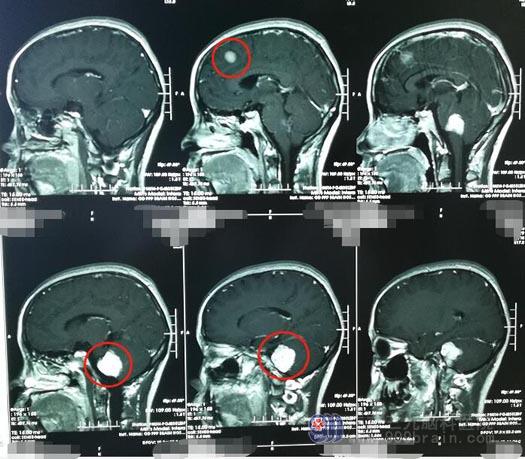

去年10月份,赵女士因为头晕伴右侧耳鸣在神经外五科治疗,头颅MR检查显示:1.右侧桥小脑角区占位性病变,考虑听神经鞘瘤可能;2.左侧额部镰旁占位性病变,考虑脑膜瘤。

主管医生告诉赵女士:颅内同时长了两个肿瘤,并且之间的距离比较远,两个肿瘤一次手术风险太大,考虑分两次进行,先将颅内下方的听神经瘤切除,待患者的身体恢复后,再切除颅内上方的脑膜瘤。这类手术在脑科医院比较常见,正常情况下,手术都能安全有效地完成。经过医生的讲解,赵女士的心里踏实多了。

2019年10月份,医院副院长、神经外五科主任鲁明带领团队为赵女士施行了“右侧桥小脑角区听神经鞘瘤切除术”。术后,赵女士没有任何并发症出现,很快便康复出院。